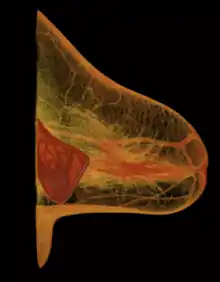

A breast implant failure: the parts of a surgically explanted breast implant are the red, fibrous capsule (left), the ruptured silicone implant (center), and the transparent filler-gel that leaked with the capsule (right).

When a silicone breast implant ruptures it usually does not deflate, yet the filler gel does leak from it, which can migrate to the implant pocket; therefore, an intracapsular rupture (in-capsule leak) can become an extracapsular rupture (out-of-capsule leak), and each occurrence is resolved by explantation. Although the leaked silicone filler-gel can migrate from the chest tissues to elsewhere in the woman's body, most clinical complications are limited to the breast and armpit areas, usually manifested as granulomas (inflammatory nodules) and axillary lymphadenopathy (enlarged lymph glands in the armpit area).[47][48][49]